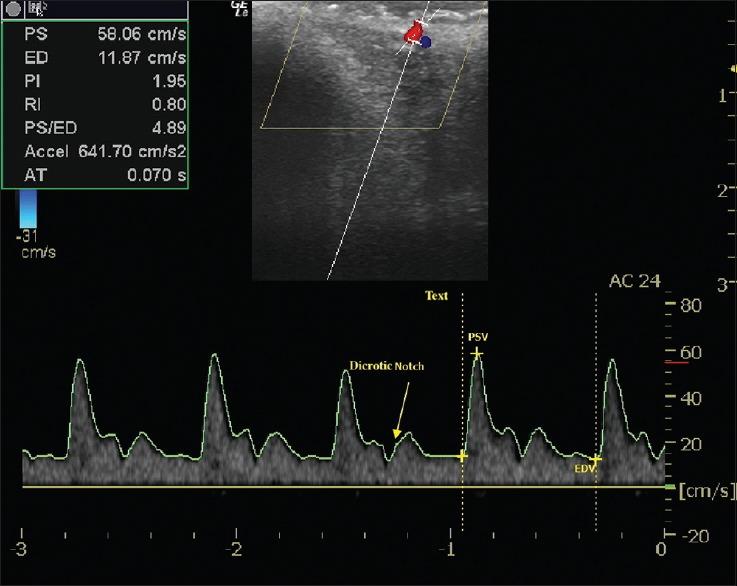

Calibre-persistent labial artery (CPLA) is a commonly underdiagnosed vascular lesion of the lip. CPLA is an arterial branch that penetrates the submucosal tissue without loss of calibre. Clinical diagnosis is significant as misdiagnosis can lead to profuse haemorrhage following an excisional biopsy or surgical excision. Colour Doppler ultrasonography is a safe and non-invasive diagnostic tool to confirm the diagnosis. Here, we report a case of a 24-year-old man who complained of an asymptomatic pulsating non-progressive nodule on the left side of upper lip initially diagnosed as peripheral angiomatous lesion. Diagnosis was confirmed by high-resolution Colour Doppler Ultrasonography. The purpose of this case report is to highlight the clinical importance and diagnosis of a rarely reported soft tissue swelling of the lip to the attention of clinicians.

口径恒定的唇动脉(CPLA)是一种常被漏诊的唇部血管病变。CPLA是一条穿透黏膜下组织且口径不变的动脉分支。临床诊断很重要,因为误诊可能导致切除活检或手术切除后大量出血。彩色多普勒超声是一种安全且无创的诊断工具,可用于确诊。在此,我们报告一例24岁男性病例,该患者主诉上唇左侧有一无症状搏动性、非进行性结节,最初被诊断为外周血管瘤样病变。通过高分辨率彩色多普勒超声确诊。本病例报告的目的是引起临床医生对这种罕见的唇部软组织肿胀的临床重要性及诊断的关注。